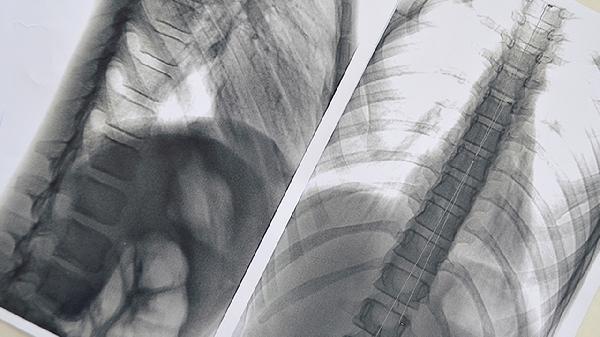

肺片状高密度影的原因是什么

肺片状高密度影可能由肺炎、肺结核、肺水肿、肺栓塞、肺肿瘤等原因引起。肺片状高密度影通常表现为咳嗽、胸痛、呼吸困难等症状,需结合影像学检查及临床表现综合判断。